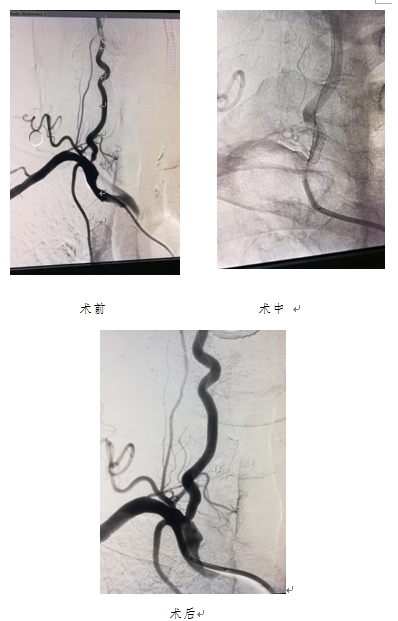

7月31日下午,神经内科完成一例右侧椎动脉起始段重度狭窄球囊扩张血管成形并支架植入术。手术的成功完成,填补了神经内科椎动脉支架植入术的空白,取得良好的治疗效果。

给患者行颈部B超显示,患者的双侧颈总动脉、颈内外动脉、右锁骨下动脉粥样硬化斑块形成,右侧颈总动脉、右侧锁骨下动脉管腔狭窄,右侧颈内动脉管腔闭塞。进一步做全脑血管造影显示,患者的右侧颈内动脉起始段闭塞;右侧椎动脉起始段重度狭窄;左侧椎动脉V4段中度狭窄。

7月31日下午,在完善各项检查及术前准备后,为患者做了右侧椎动脉起始段重度狭窄球囊扩张血管成形并支架植入术。

整台手术历时约40分钟,在右侧椎动脉狭窄处顺利植入支架。术中术后患者生命体征平稳,无其他不适。